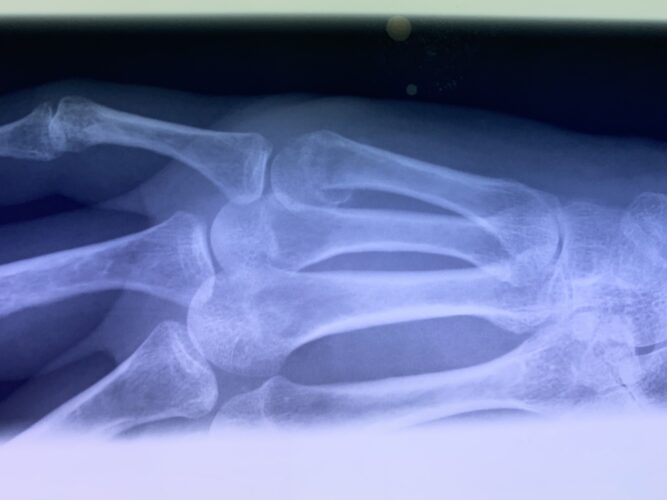

第16回整骨研究会「賜恩」研修会開催

さわやか千葉県民プラザ(指骨骨折)

第18回整骨研究会「賜恩」研修会開催

第20回整骨研究会「賜恩」研修会開催

さわやか千葉県民プラザ(指の脱臼)